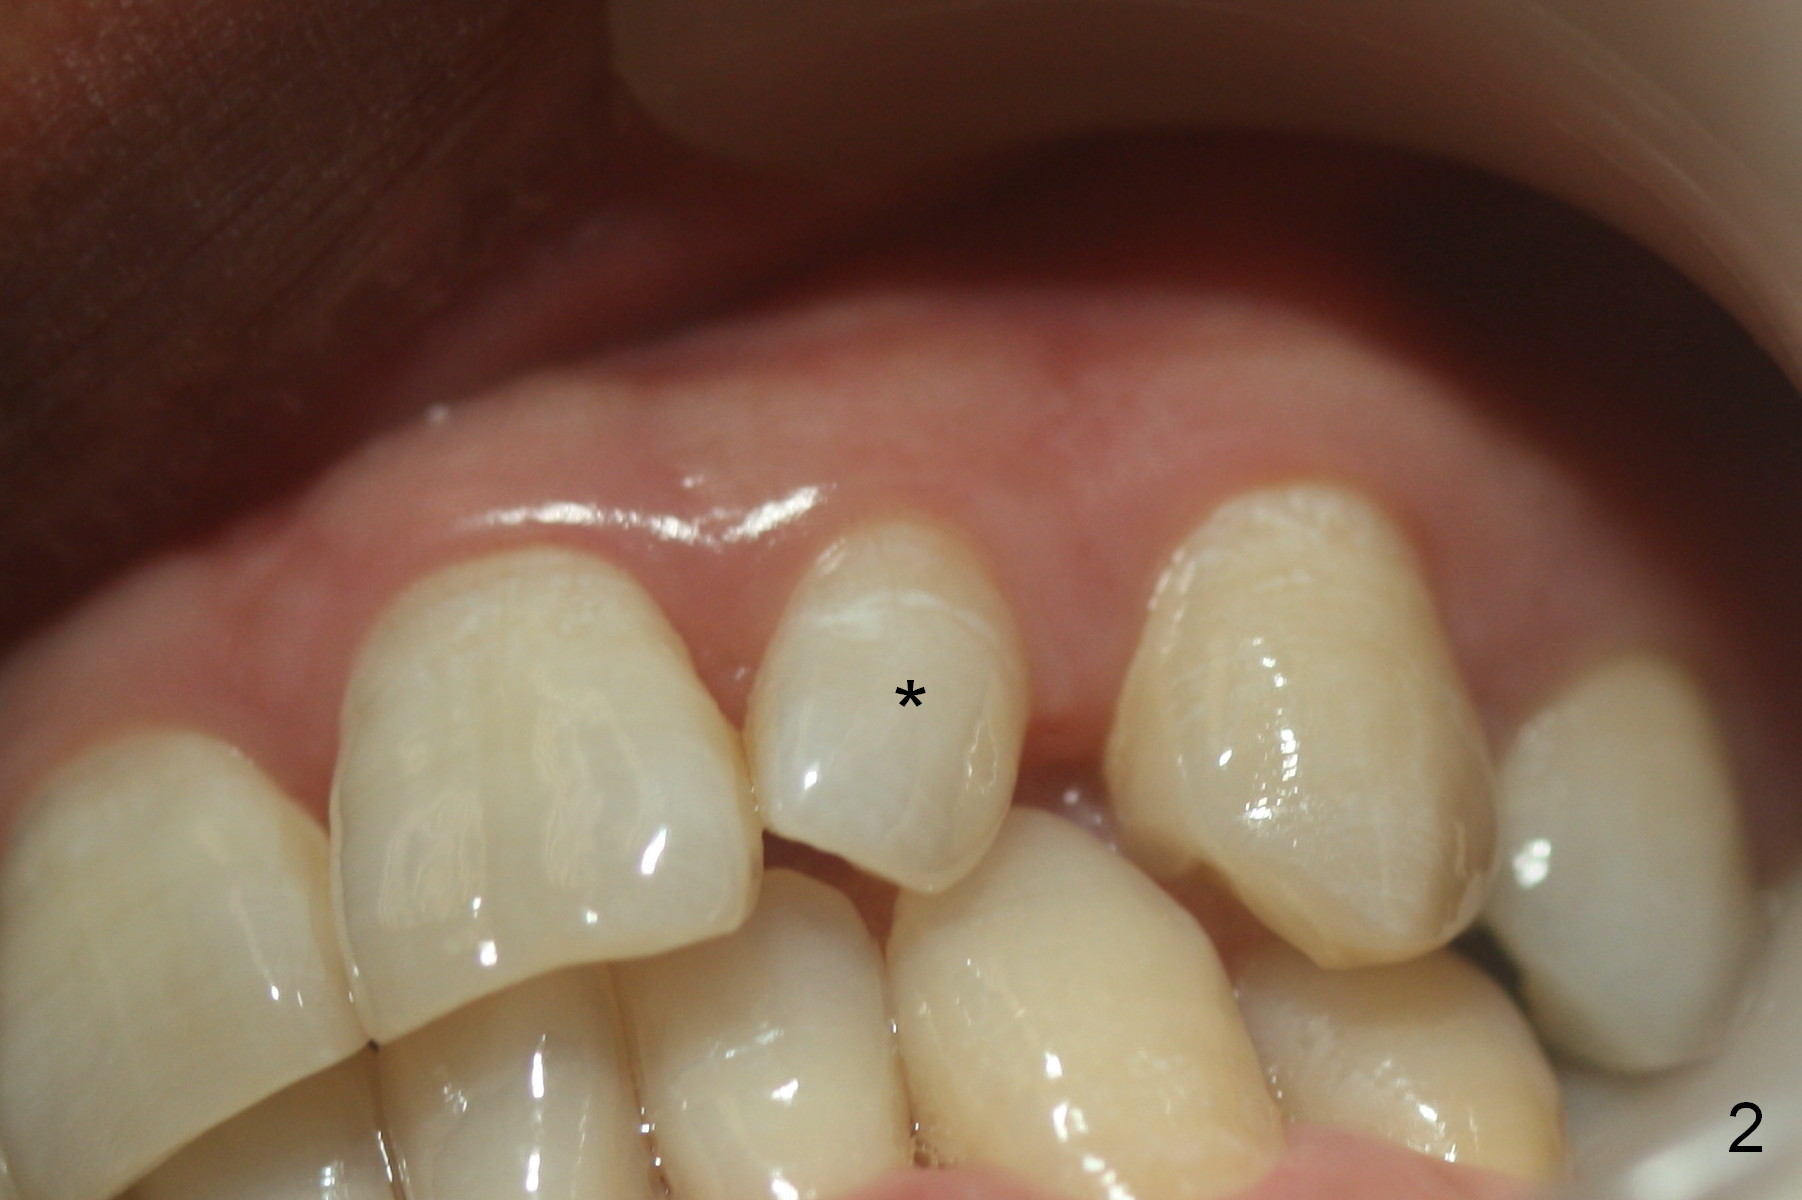

| Before |

A 36-year-old man has 2 small, congenitally deformed lateral incisors (peg laterals, Fig.1,2 *). After discussion, we choose porcelain veneers for cosmetic makeup. The teeth need minor shaving (Fig.3,4); right colors are being selected with a shade guide (Fig.4: G). The shaving is so conservative that there is no pain during the procedure and there is no need to make temporary veneers. One to 2 weeks later, porcelain veneers are cemented (Fig.5,6). The patient is satisfied.